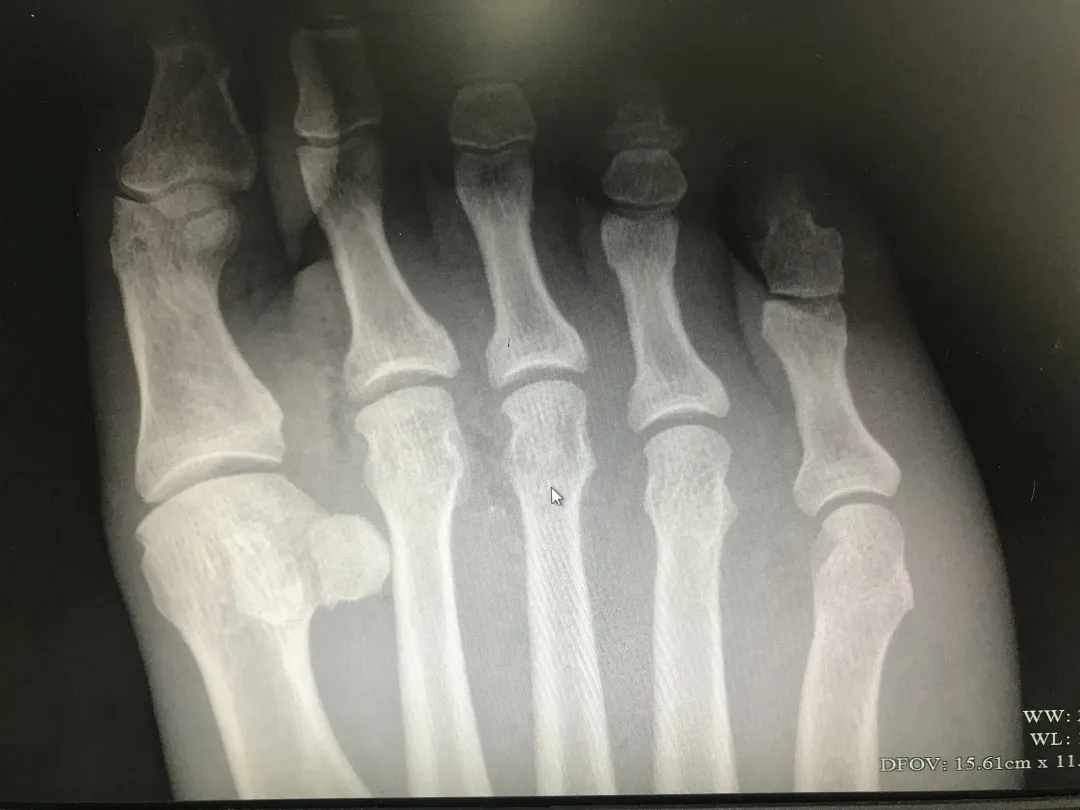

足部伤口虽小,也要注意

生活中,不少朋友因赤脚或意外,导致足部被扎伤,往往贴张创口贴,毫不在乎,但实际上,即使是小伤口,也有造成严重后果的可能。

此前,据义乌市中心医院,务农的刘大爷只是在田里干农活时不慎被异物扎伤了一下,竟然严重到差点要截肢。当时自己也没在意,赶紧拔出来就扔了。结果就因为没有及时就医,感染的情况非常严重,右足第二趾已完全坏死,最终,刘大爷的右足虽然保住,但切除了完全坏死的右足第二趾,又进行了游离皮瓣移植术。

另外,如果被生锈的钉子扎伤,可能会导致破伤风感染,需要到正规医院进行治疗,必要时注射破伤风疫苗或破伤风针。

建议大家在日常生活中加强防护,尽量不要光脚,遭遇扎伤、刺伤、擦伤,一旦发现异常情况,一定要及时到正规专科医生处进行治疗。

同时,也要特别提醒老人及其家属,由于老人脚底血供较差,异物扎伤后表皮伤口不大、出血量不多,更易忽视,如出现扎伤等情况,一定要及时就医,以免出现不良后果。